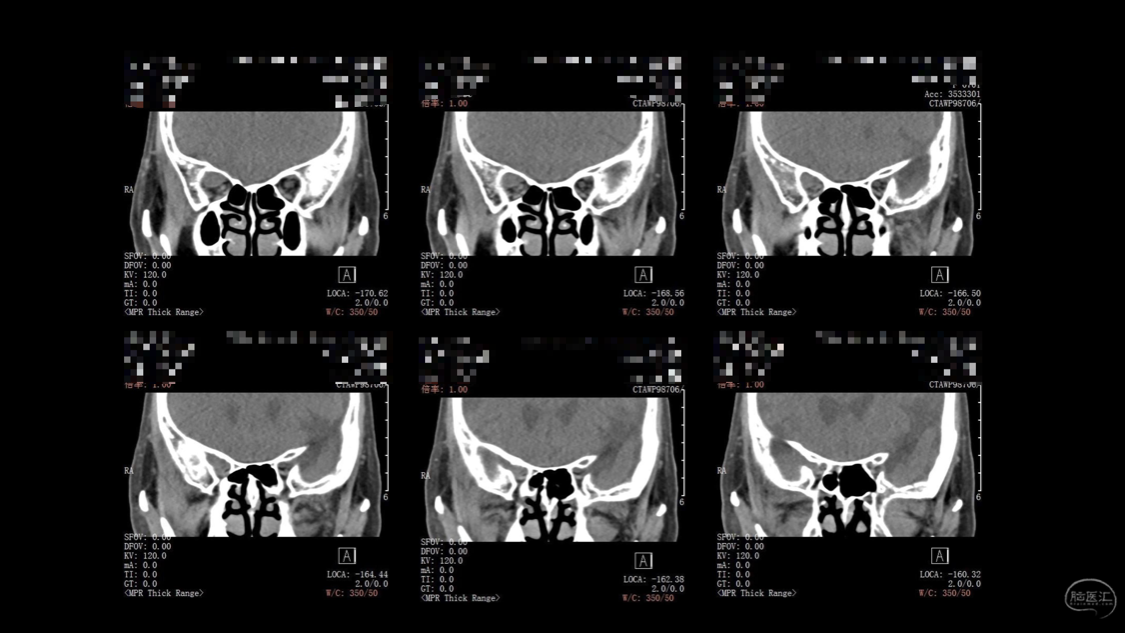

陈保东教授手术作品-右眶内及海绵窦旁孤立性纤维瘤